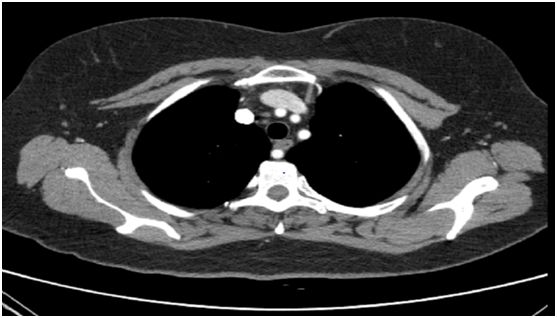

“巨大的瘤体上至甲状软骨上极、下至胸骨后主动脉弓水平,并且有三分之二的瘤体在胸骨后,气管严重受压变形”,代文杰教授为患者完善检查后发现李某甲状腺增大明显。李女士体型相对较胖,脖子较短,且合并甲亢,腺体血供丰富,手术风险巨大。

▲甲状腺CT影像显示气管受压,腺体下缘达到主动脉弓水平,2/3腺体位于胸骨后

由于肿瘤巨大,瘤体的三分之二居胸骨后,若术中进展不顺利,则需要劈开胸骨才可成功将腺体完整切除,并且患者脖子短、体型胖,使得经颈横切口切除巨大甲状腺肿瘤更为困难。除此以外患者高龄,伴有甲状腺功能亢进,不充分的术前准备、不轻柔的术中操作很容易引起术后甲状腺危象,一旦发生可在短时间内发展至昏迷、休克,甚至要了命。